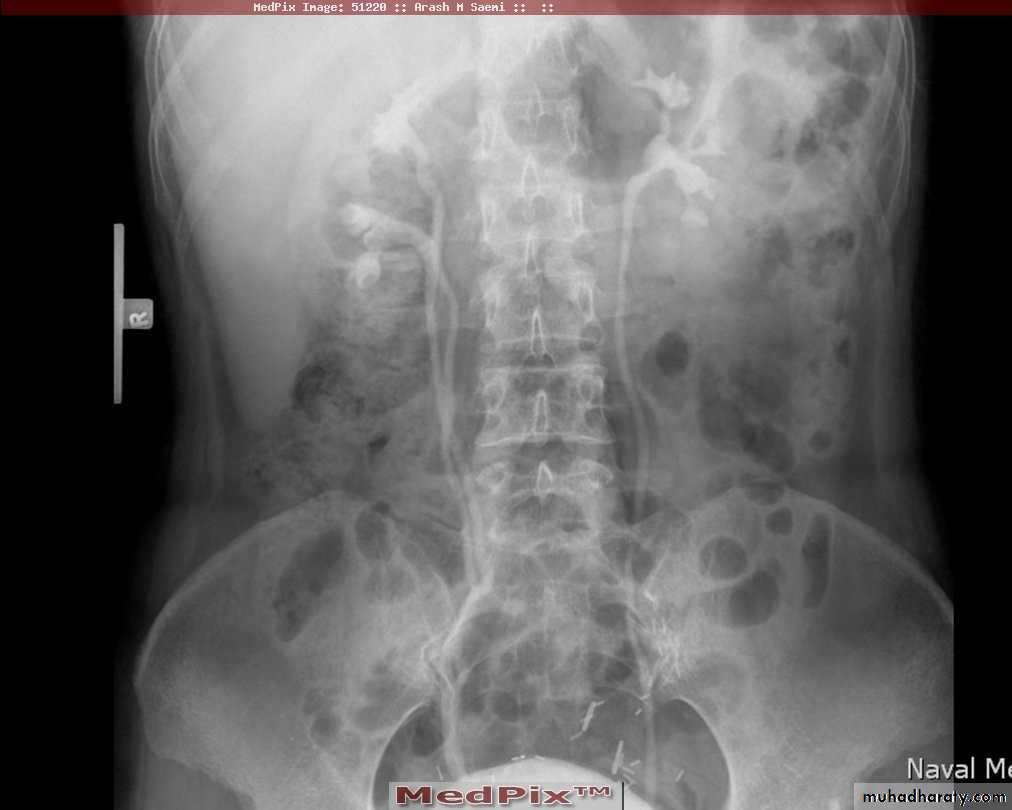

*Polycystic kidney disease